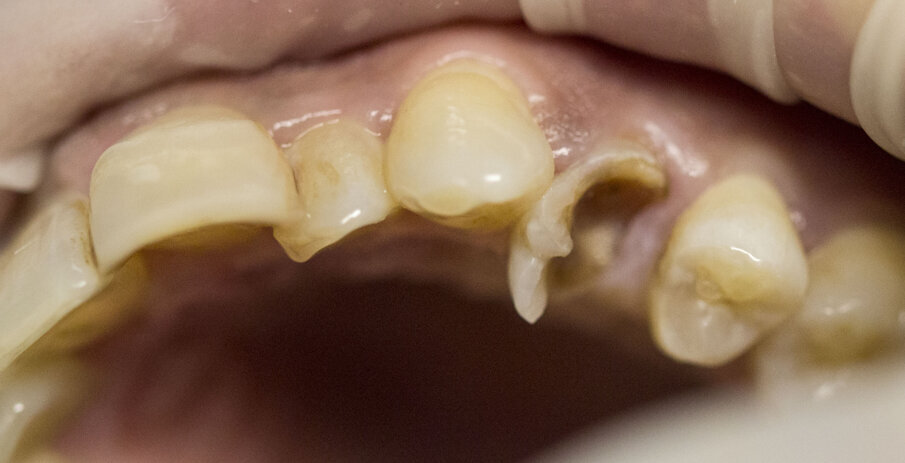

Fig. 3 - Dente fratturato 2.4.

Fig. 4 - Estrazione del dente 2.4.